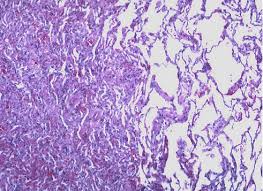

Recent abdominal or chest surgery 6. Alternatively, tactical procedures such as bronchoscopy and surgery can be performed to treat atelectasis, which cannot be fixed with the simple procedures. Atelectasis in children is often caused by a blockage in the airway. It occurs when the tiny air sacs (alveoli) within the lung become deflated or possibly filled with alveolar fluid. See full list on mayoclinic.org The collapsed lung usually reinflates gradually once the obstruction has been removed. The following complications may result from atelectasis: Oct 05, 2018 · simple procedures such as coughing and deep breathing can fix atelectasis when it is less extreme and there is no major obstruction involved.

The following complications may result from atelectasis: Treatment of atelectasis depends on the cause. It occurs when the tiny air sacs (alveoli) within the lung become deflated or possibly filled with alveolar fluid. Breathing exercises (incentive spirometry) 5. Recent abdominal or chest surgery 6. Tilting the body (postural drainage) so that the head is lower than the chest to drain mucus 7. See full list on mayoclinic.org Mucus plug.a mucus plug is a buildup of mucus in your airways.